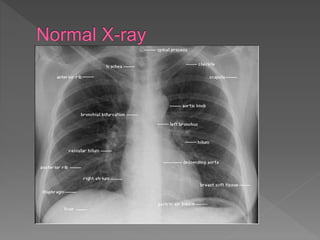

 A - Airway

 Trachea is visible and in midline

 Trachea gets pushed away from abnormality,

e.g. pleural effusion or tension pneumothorax

 Trachea gets pulled towards abnormality, e.g.

atelectasis

 Trachea normally narrows at the vocal cords

 View the carina, angle should be between 60 –

100 degrees

 B – Bones

 Check for fractures, dislocation, subluxation,

osteoblastic or osteolytic lesions in clavicles,

ribs, thoracic

 Spine and humerus including osteoarthritic

changes

 At this time also check the soft tissues for

subcutaneous air, foreign bodies and

surgical clips

 C - Cardiac

 Check heart size and heart borders

 Heart position –⅔ to left, ⅓ to right

 Heart size – measure cardiothoracic ratio on PA

film (normal <0.5)

 Heart borders – R) border is R) atrium, L)

border is L) ventricle & atrium

 D – Diaphragm

 Right hemi-diaphragm o

 Should be higher than the left o(~2.5cm / 1

intercostal space)

 If much higher, think of effusion, lobar

collapse, diaphragmatic paralysis o

 If you cannot see parts of the diaphragm,

consider infiltrate or effusion

 E – Effusion

 Effusions o Look for blunting of the

costophrenic angle

 Identify the major fissures, if you can see

them more obvious than usual, then this

could mean that fluid is tracking along the

fissure

 Check out the pleura

 Thickening, loculations, calcifications and

pneumothorax